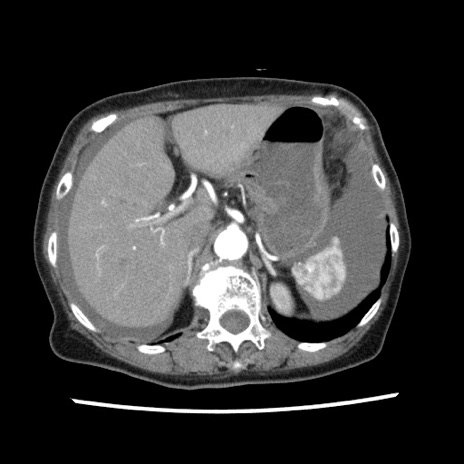

冠状断像

【症例】80歳代女性

【主訴】腹痛

【現病歴】8時間前から腹痛あり来院。

【既往歴】糖尿病、脂質異常症、子宮体癌にて子宮全摘術

【身体所見】意識清明・会話良好だが腹痛で苦悶様、全腹部にわたって反跳痛と圧痛あり

【データ】WBC 13600、CRP 0.14、LDH 224、CK 90